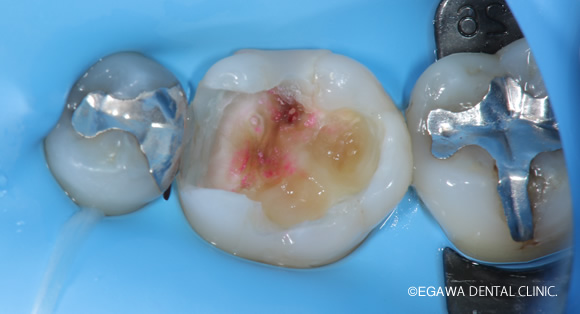

こだわり:ラバーダム防湿

ラバーダム防湿を事前に施しマイクロスコープを覗いてしっかり根管治療をします。

クランプなども多用し、ラバーダム防湿も複雑になりますが、これだけの手間暇をかけてしっかり接着修復しています。